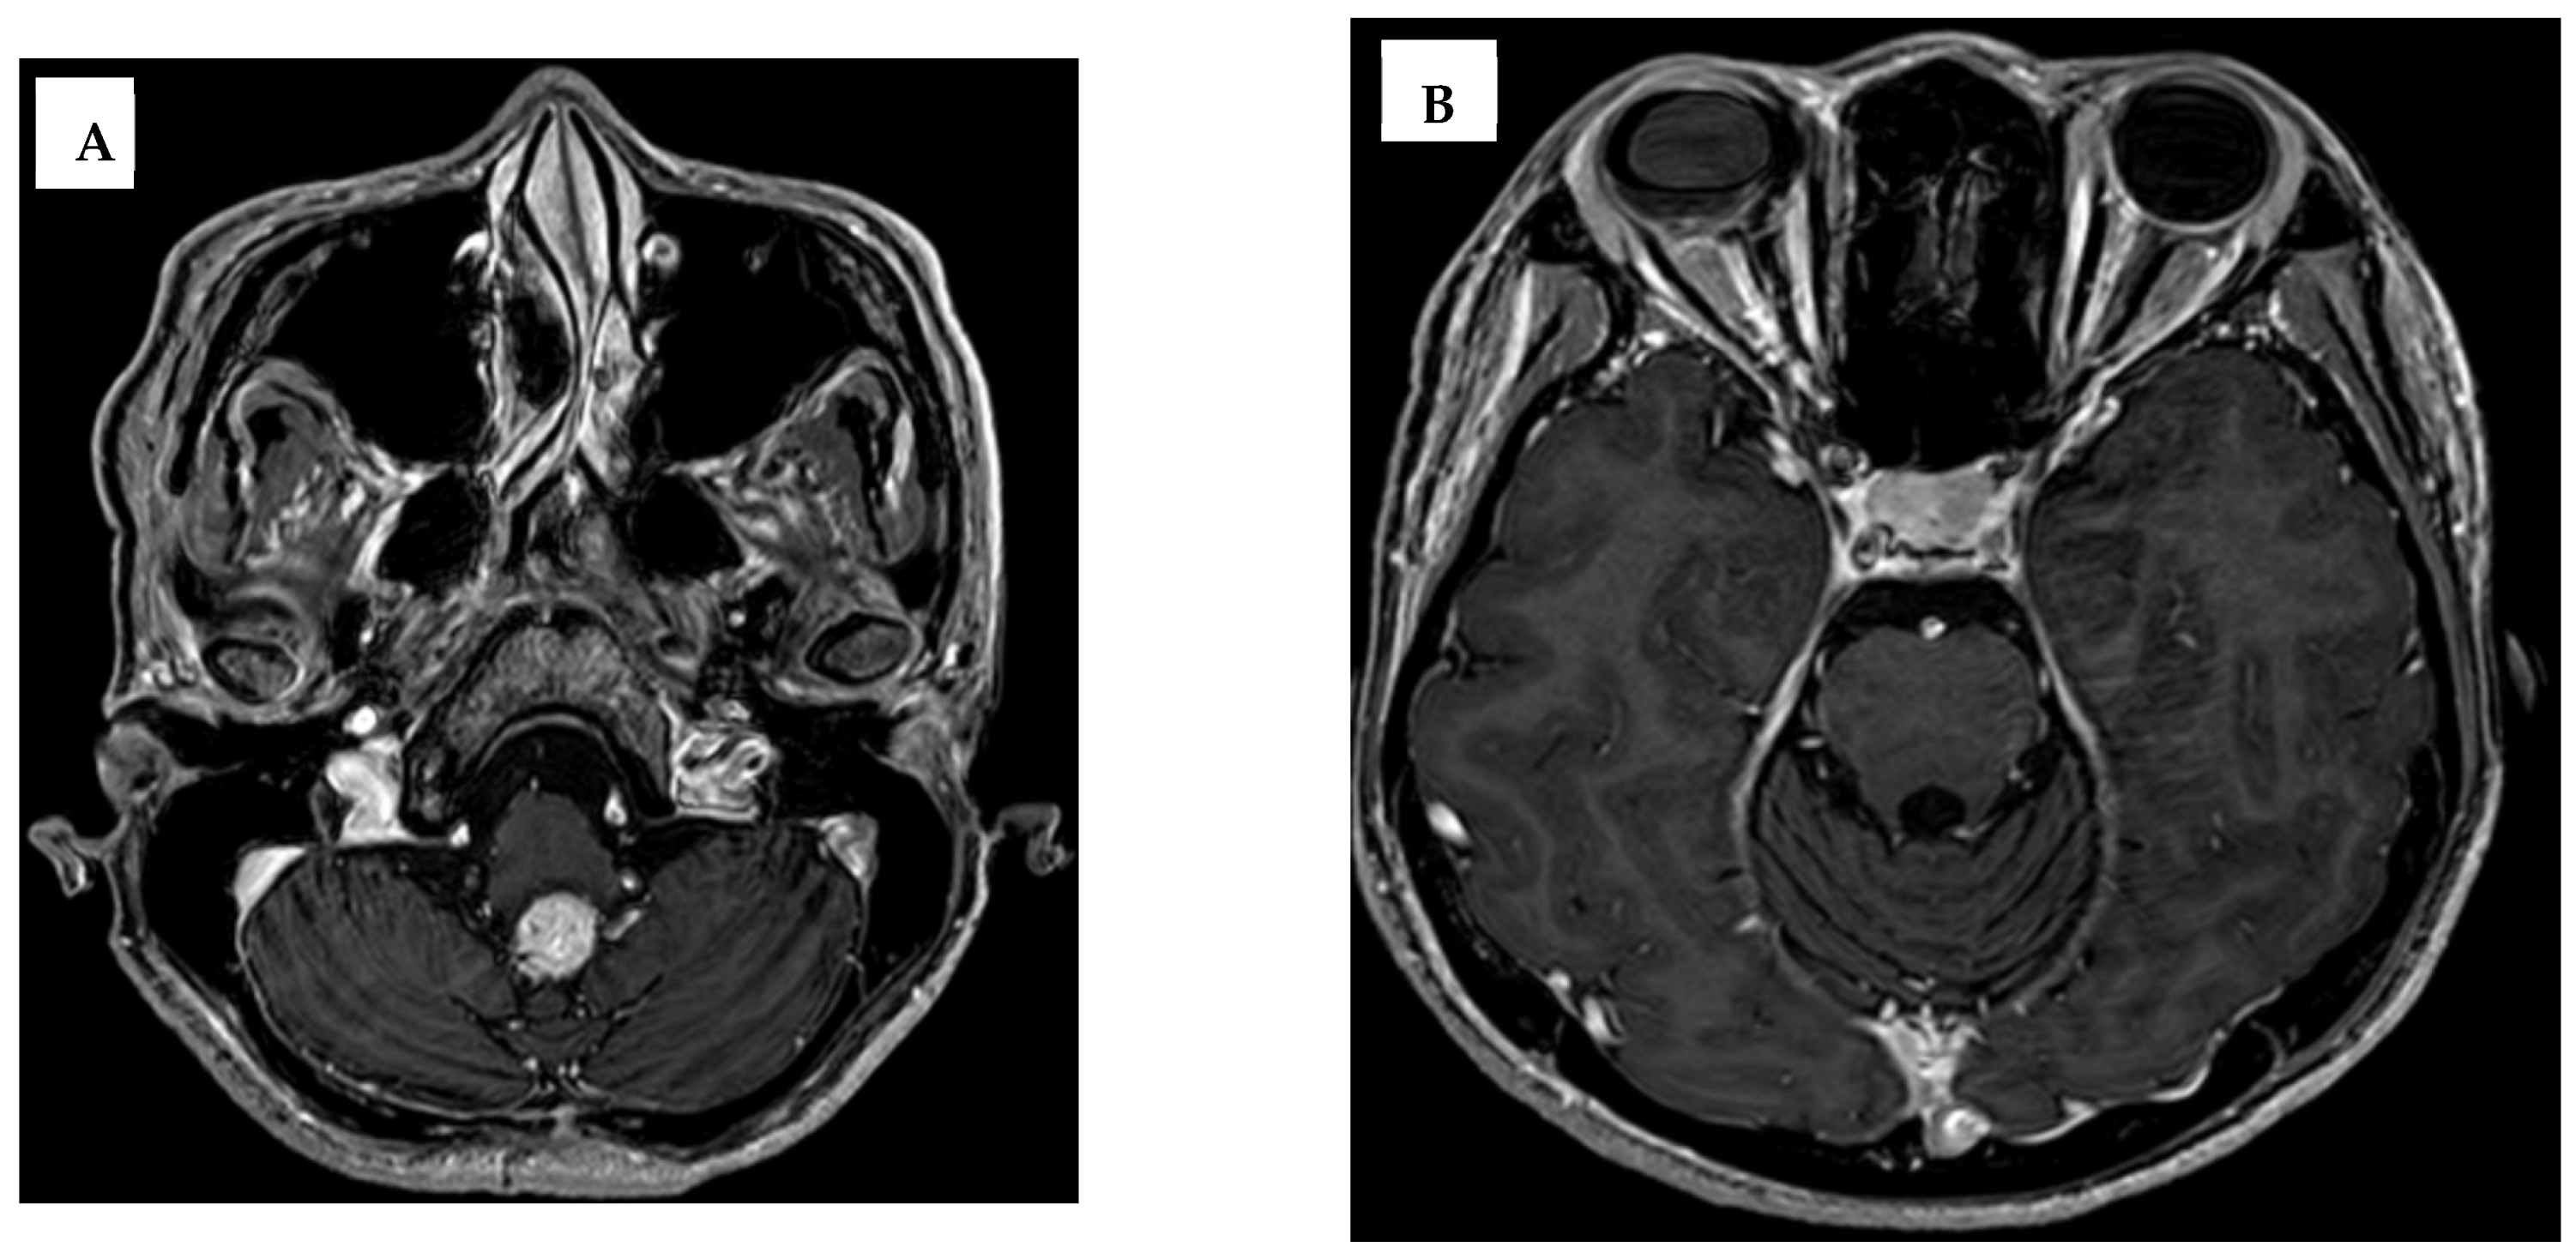

2. Case Report

| Time Point | 4th Ventricular Lesion | Retrobulbar Lesion | Spinal Lesions | Notes |

|---|---|---|---|---|

| Initial (Year 0) | 19 mm | 11 mm | Not checked | Pre-GKS |

| After two GKS sessions (Year 1) | 12 mm | 11 mm | Not checked | Partial regression |

| Lost to follow-up (Year 3) | 12 mm | 11 mm | Detected nodules in C1-C2, C6 and T8 | Progression |

| Post-progression imaging | Stable | Stable | Multiple | Observation phase |

| Final follow-up (Year 9) | Stable | Stable | Stable | Conservative management |